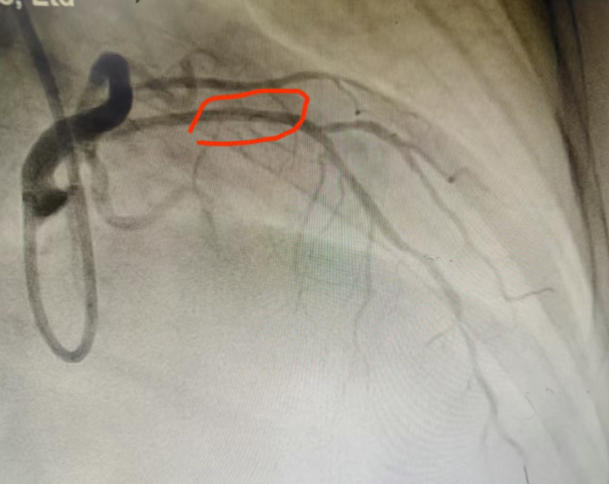

"若不打通堵塞的血管,心衰随时会复发。"心内二科马东亮主任判断患者心脏最重要的血管前降支存在严重狭窄。经与家属深入沟通,导管室团队为患者实施冠脉造影,结果证实前降支近段堵塞超过90%。通过微创介入药物球囊扩张成形术,团队成功开通病变血管,术后患者心脏功能得到根本改善。

术前